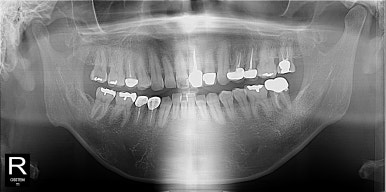

60대 환자분이 이런얘기를 하면 10년 전만해도 불편한 것도 없으신데 굳이 교정을 하셔야할까요? 넌지시 물었었다. 근데 나도 나이가 들면서 이런 생각을 한다. 왜? 나이가 들어서 보기 싫은 건 더 고쳐서 더 자신있게 예쁘게 건강하게 살고 싶은걸.. 니들이 뭘 안다고

그런것 같다. 그래서 네 그게 불만이고 콤플렉스라면 앞니만 간단히 6-7개월 투자하셔서 (당연히 이점이 있다) 대신 그 불편한 기간은 잘 견뎌주셔야 한다고

대부분의 환자분들은 예뻐지는 내 이를 직접보니 잘 견디시는 것 같다.

발치 전 사진이 없어서 아쉽지만... 이렇게 한 개 치아를 반드시 발치해야하고 주변치아들이 비뚤다면 정말 교정이 답이 될 수 있다는 생각이 든다. 잇몸이 너무 좋지 않아서 잇몸공간이 눈에 띄기는 하지만 이후 치주 관리도 잘하시고 유지장치로 앞니끼리 고정되어 있으니 예상보다 오래 잘 쓰시고 계신다..